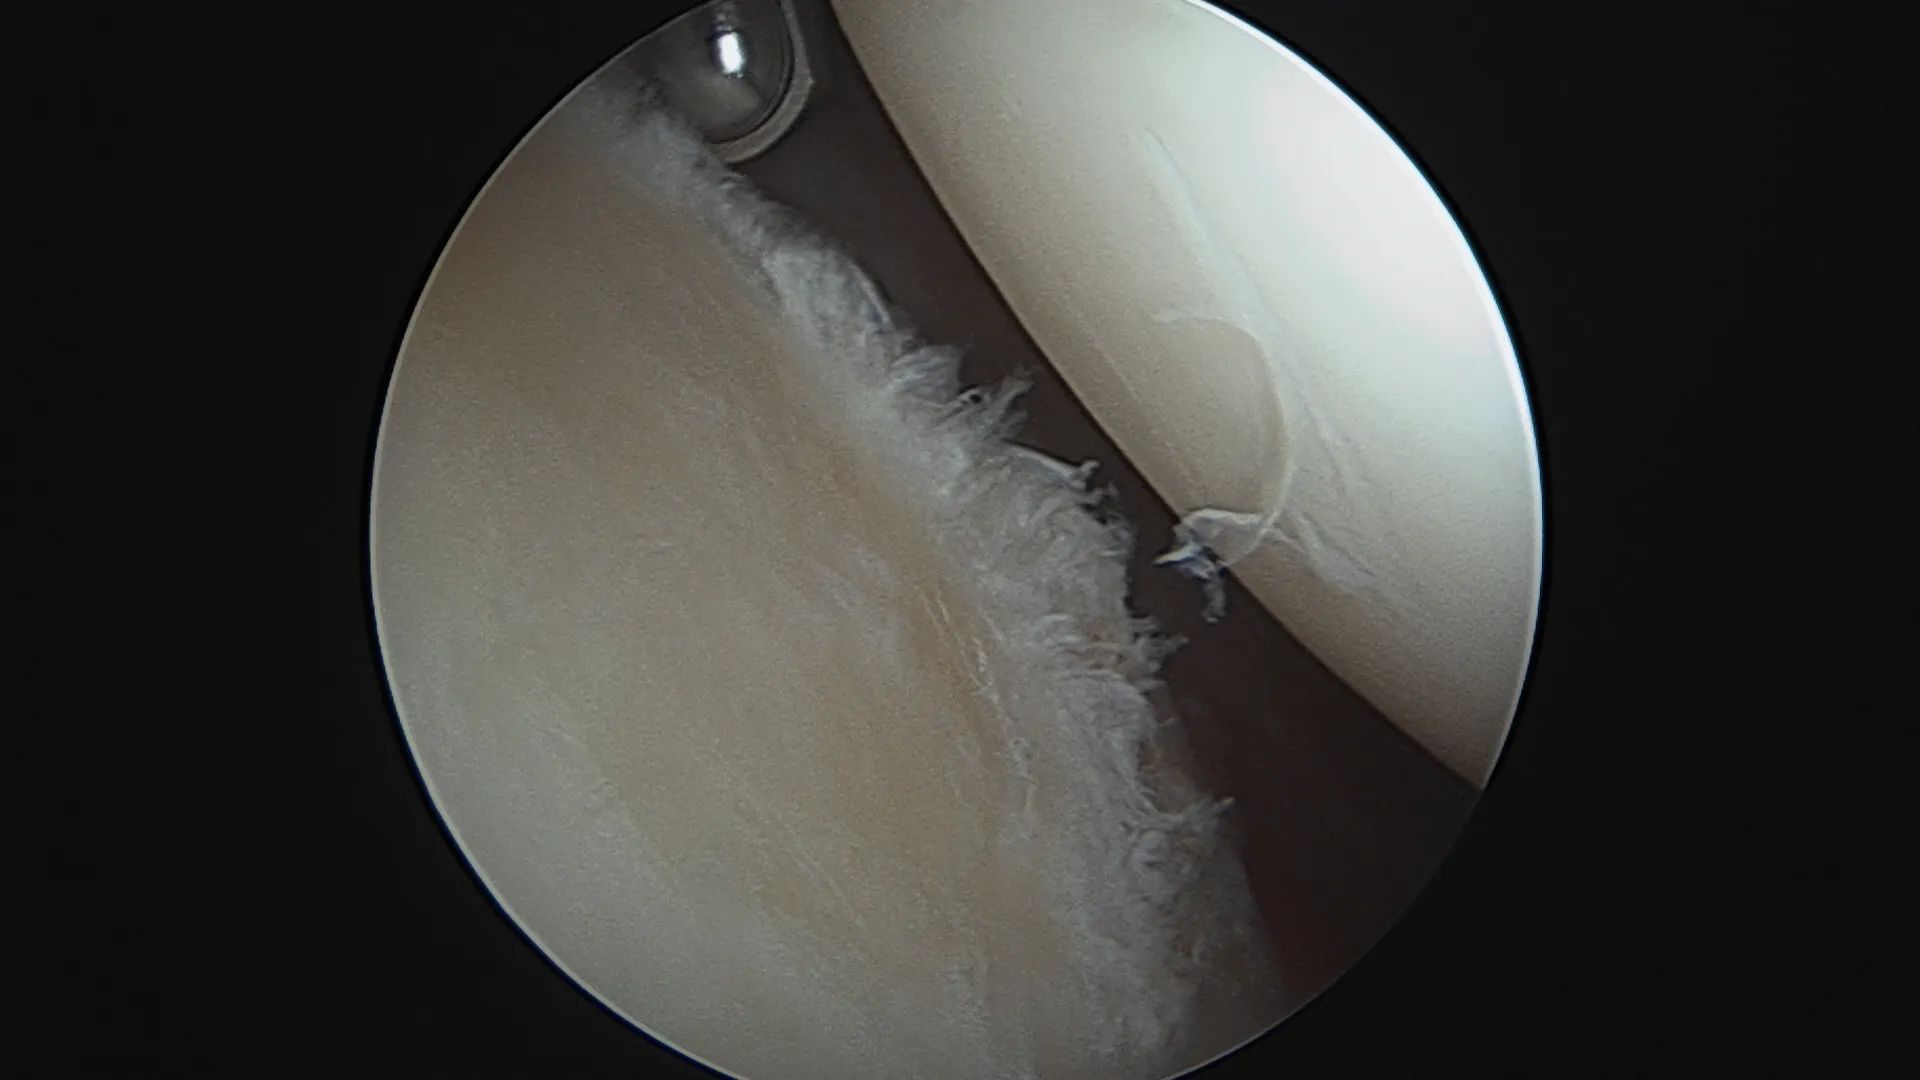

La lésion de Bankart

Le labrum se détache de la surface osseuse glénoïdienne. C'est la lésion la plus fréquente. Elle peut cicatriser spontanément — surtout après un premier épisode chez un patient jeune bien immobilisé. En cas de récidive, cette cicatrisation devient improbable.

Réparation de Bankart — sous arthroscopie

Pour qui ? Instabilité antérieure sans perte osseuse glénoïdienne significative (score ISIS ≤ 3).

Comment ? L'intervention est réalisée entièrement sous arthroscopie (vidéochirurgie), par 2 à 3 incisions de quelques millimètres seulement. Le labrum arraché est réinséré sur la glène à l'aide d'ancres résorbables sur lesquelles sont fixés des fils très résistants. Les ligaments gléno-huméraux distendus sont retendus dans le même temps opératoire.